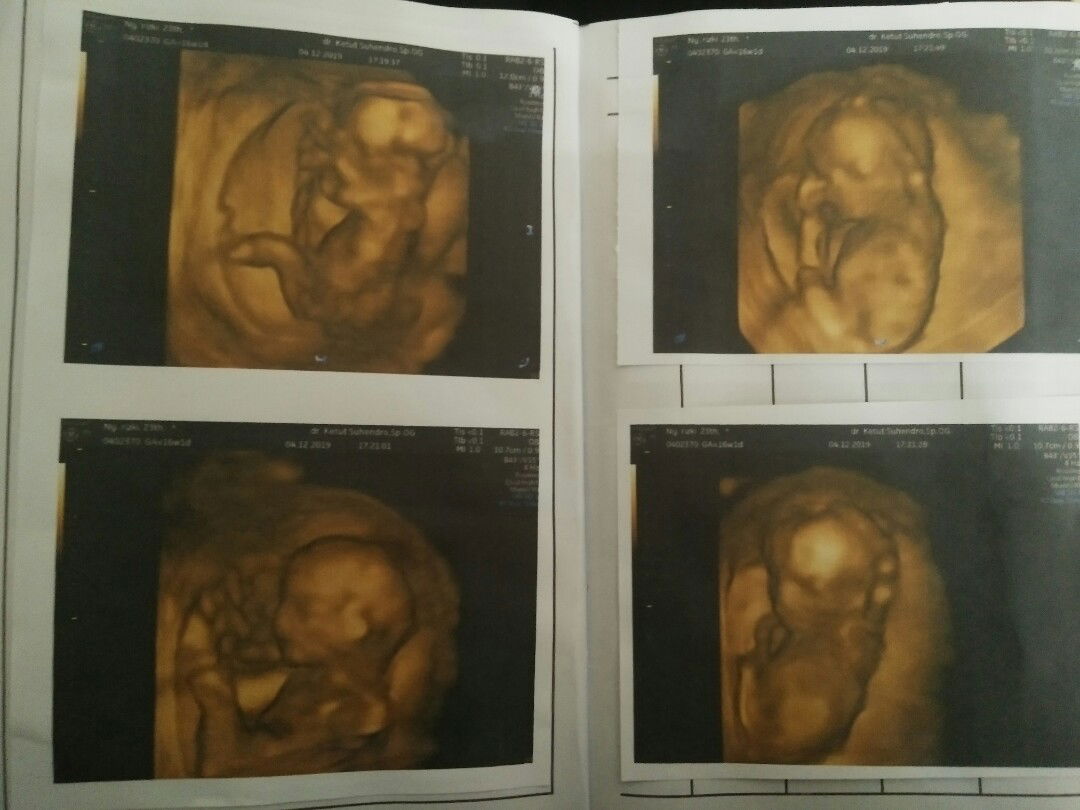

Usg ketika 16 W

USG 20 W

Usia 20 week apakah udah bisa keliatan jenis kelamin kalo di usg?